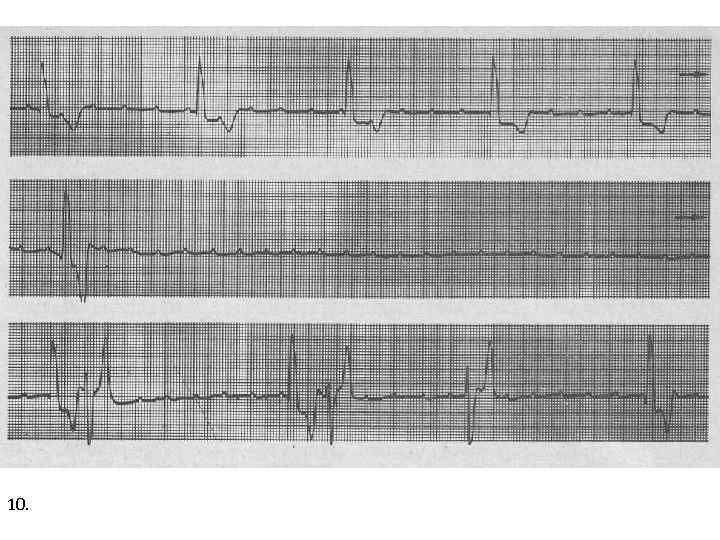

10.